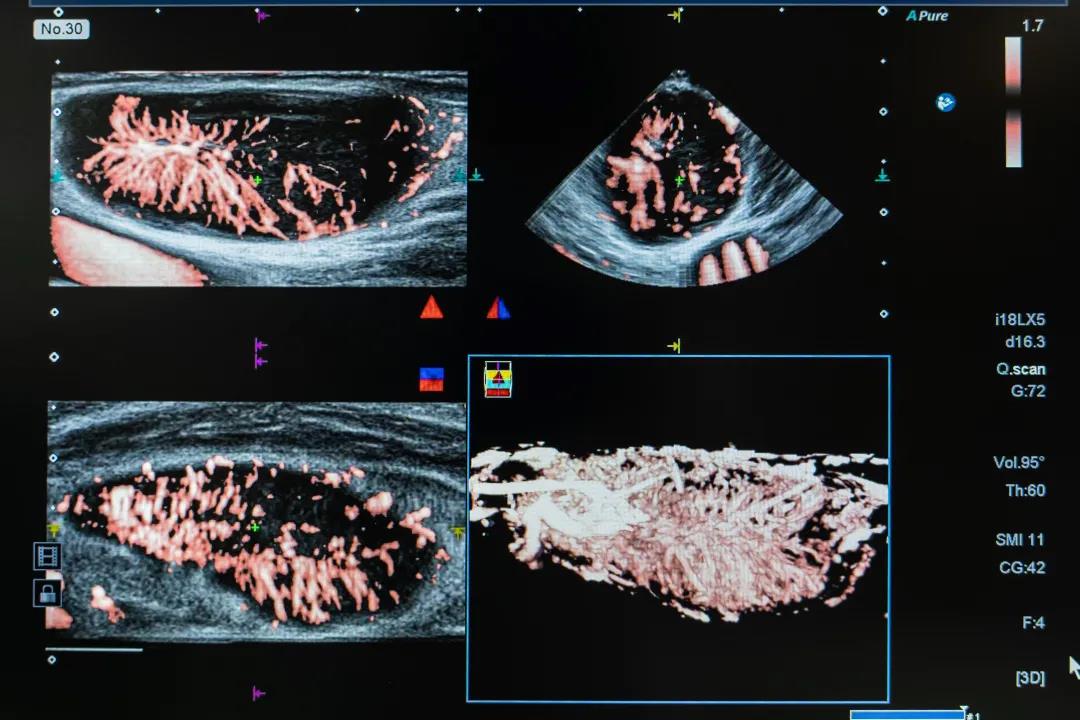

Aplio i900 SMI技术显示淋巴结里的血流

该设备配备的超微血流成像技术SMI可精确呈现人体血流动力学的信息,广泛应用于腹部、小器官包括肌骨皮肤、外周血管等方面,如肝脏、肾脏、膀胱等器官良恶性肿瘤的诊断、肝肾移植术前术后评估、甲状腺乳腺良恶性肿瘤的诊断、乳腺癌患者前哨淋巴结的观察、类风湿关节炎的诊断与治疗效果的随访观察,肌肉骨骼肿瘤诊断及介入治疗疗效评估等。